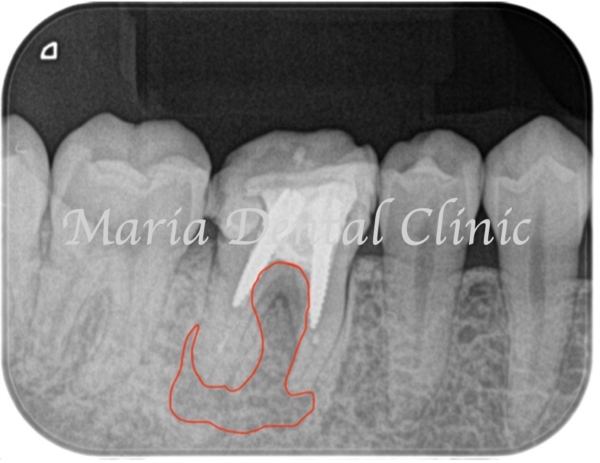

術前の写真を確認すると根の先端から広がる病変の影は歯の股の部分まで大きくなっていることが確認できます(術前写真②)

通法通り根管治療を施したことで歯ぐきの腫脹は改善したものの、分岐部(歯の股の部分)の歯周病に治癒傾向は確認されず(写真1術前)歯周病の治療に移行する判断をしました。

歯周病専門医による組織再生療法を行なった際にはレントゲンで透過像(黒い影)があった歯の股の部分の骨は著しく欠損していました(写真2術中)。骨の欠損部分に組織再生治療を行い、さらに3ヶ月の経過観察を行い生体の治癒を待ちました。